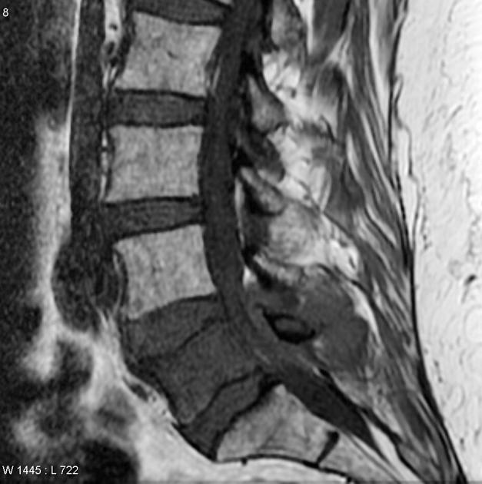

Spine Synovial Cysts MRI

Extramedullary Intradural

- dermoid

- epidermoid

- meningioma

- neurofibroma